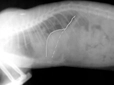

Diyafram Hernisi Ameliyatı ve SonrasıDiyafram hernisi, diyafram kaslarının zayıflaması veya yaralanması sonucunda abdominal organların göğüs boşluğuna kayması durumudur. Bu rahatsızlık genellikle doğuştan olabileceği gibi, travma veya cerrahi işlemler sonrasında da gelişebilir. Diyafram hernisi ameliyatı, bu durumu düzeltmek ve hastanın yaşam kalitesini artırmak amacıyla gerçekleştirilen bir cerrahidir. Diyafram Hernisi Nedir? Diyafram, göğüs boşluğunu karın boşluğundan ayıran önemli bir kastır. Normalde, diyafram kaslarının güçlü ve sağlam olması gerekir. Ancak çeşitli faktörler, diyaframın zayıflamasına neden olabilir ve bu da diyafram hernisi ile sonuçlanabilir. Diyafram hernisinin belirtileri arasında şunlar bulunmaktadır:

Ameliyat Süreci Diyafram hernisi ameliyatı, genellikle genel anestezi altında yapılır. Ameliyat süreci aşağıdaki aşamalardan oluşmaktadır: